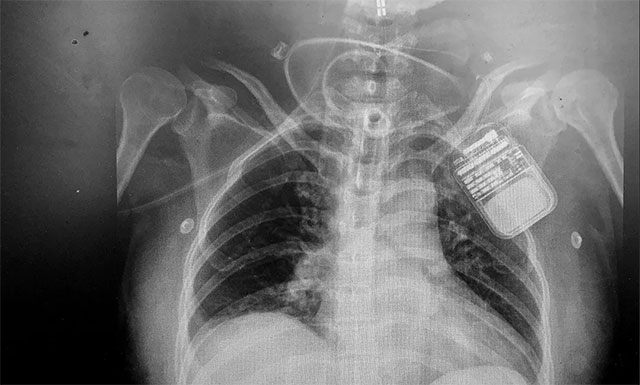

▲ 电刺激器顺利置入患者脊髓上方